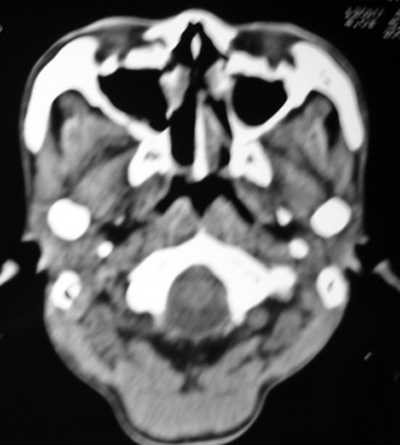

以下是引用syfszcw在2009-4-23 13:21:00的发言:[br]双侧上颌窦 筛窦慢性炎症,鼻息肉 会厌ca[br][br][本贴已被 syfszcw 于 2009-4-23 13:36:46 修改过]

以下是引用随光逐影在2009-4-23 19:35:00的发言:[br]1)鼻咽、口咽、左侧鼻腔及右侧鼻后孔处新生物,考虑息肉可能性大。2)双侧上颌窦及双侧筛窦炎症,不排除双侧上颌窦内息肉可能。